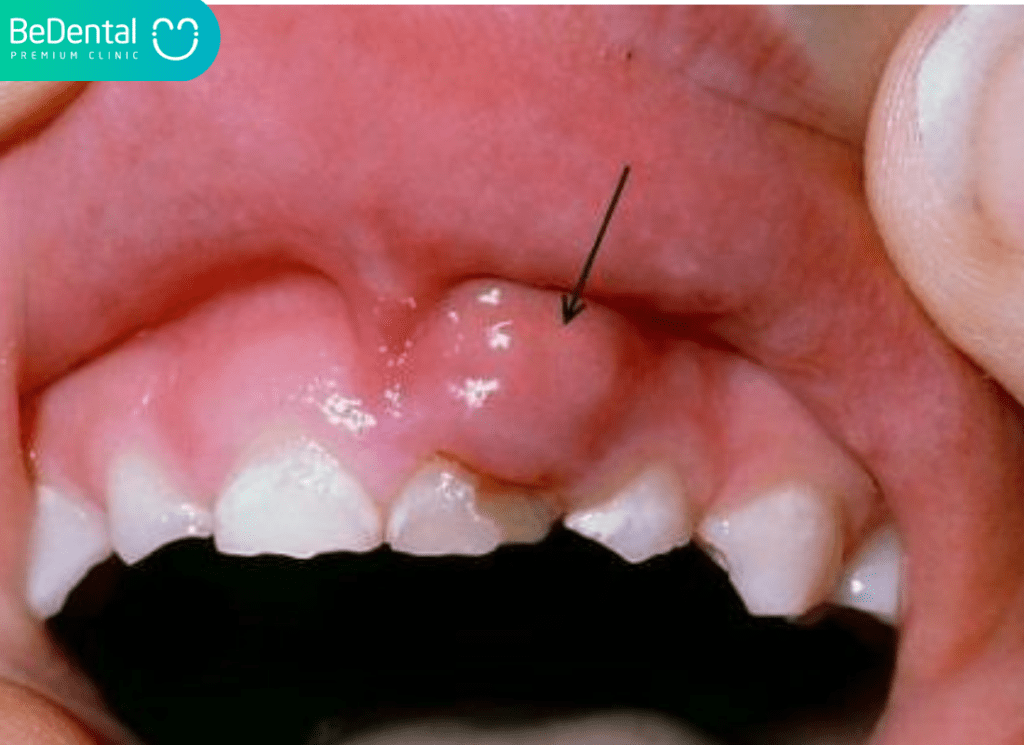

Để hiểu rõ về tình trạng này, trước hết chúng ta cần định nghĩa sưng mộng răng là một dạng viêm nhiễm nặng tại vùng nướu (lợi), nơi các mô mềm quanh răng bị tấn công bởi vi khuẩn. Khi vi khuẩn xâm nhập và trú ngụ lâu ngày trong các kẽ răng hoặc túi lợi, cơ thể sẽ kích hoạt hệ thống miễn dịch để chống lại, dẫn đến phản ứng viêm. Kết quả là vùng nướu bị phồng to, có màu đỏ thẫm và thường xuất hiện một ổ mủ dưới chân răng.

Cụm từ “mộng” trong dân gian thực chất dùng để chỉ các ổ áp xe hoặc túi mủ hình thành từ các tế bào bạch cầu chết, vụn thức ăn và vi khuẩn. Sưng mộng răng không chỉ đơn thuần là viêm lợi nhẹ mà thường là giai đoạn tiến triển của bệnh nha chu. Tình trạng này có thể xuất hiện tại bất kỳ vị trí nào trên cung hàm, nhưng phổ biến nhất vẫn là sưng mộng răng hàm do đây là khu vực khó vệ sinh nhất, dễ tích tụ mảng bám và thường gắn liền với sự mọc lệch của răng khôn.

- Nướu sưng đỏ và phồng to: Vùng lợi xung quanh răng không còn màu hồng nhạt khỏe mạnh mà chuyển sang đỏ thẫm hoặc tím nhạt. Nướu căng bóng, mất đi các gai lợi và có cảm giác đau nhói khi chạm vào.

- Xuất hiện túi mủ: Đây là dấu hiệu nhận biết rõ nhất của “mộng răng”. Bạn có thể thấy một nốt mụn nhỏ chứa dịch trắng hoặc vàng ngay trên lợi. Khi ấn nhẹ, mủ có thể thoát ra kèm theo mùi hôi và vị đắng trong miệng.

Theo số liệu thống kê từ nha khoa Bedental năm 2025, có đến 85% người trưởng thành gặp các vấn đề về viêm nướu ở các mức độ khác nhau. Trong đó, khoảng 30% bệnh nhân tìm đến phòng khám trong tình trạng sưng mộng răng đã chuyển sang giai đoạn áp xe, yêu cầu can thiệp dẫn lưu mủ và điều trị tủy. Đặc biệt, tỷ lệ sưng mộng răng hàm liên quan đến răng khôn chiếm tới 45% tổng số ca viêm nhiễm nướu tại khu vực răng hàm lớn.